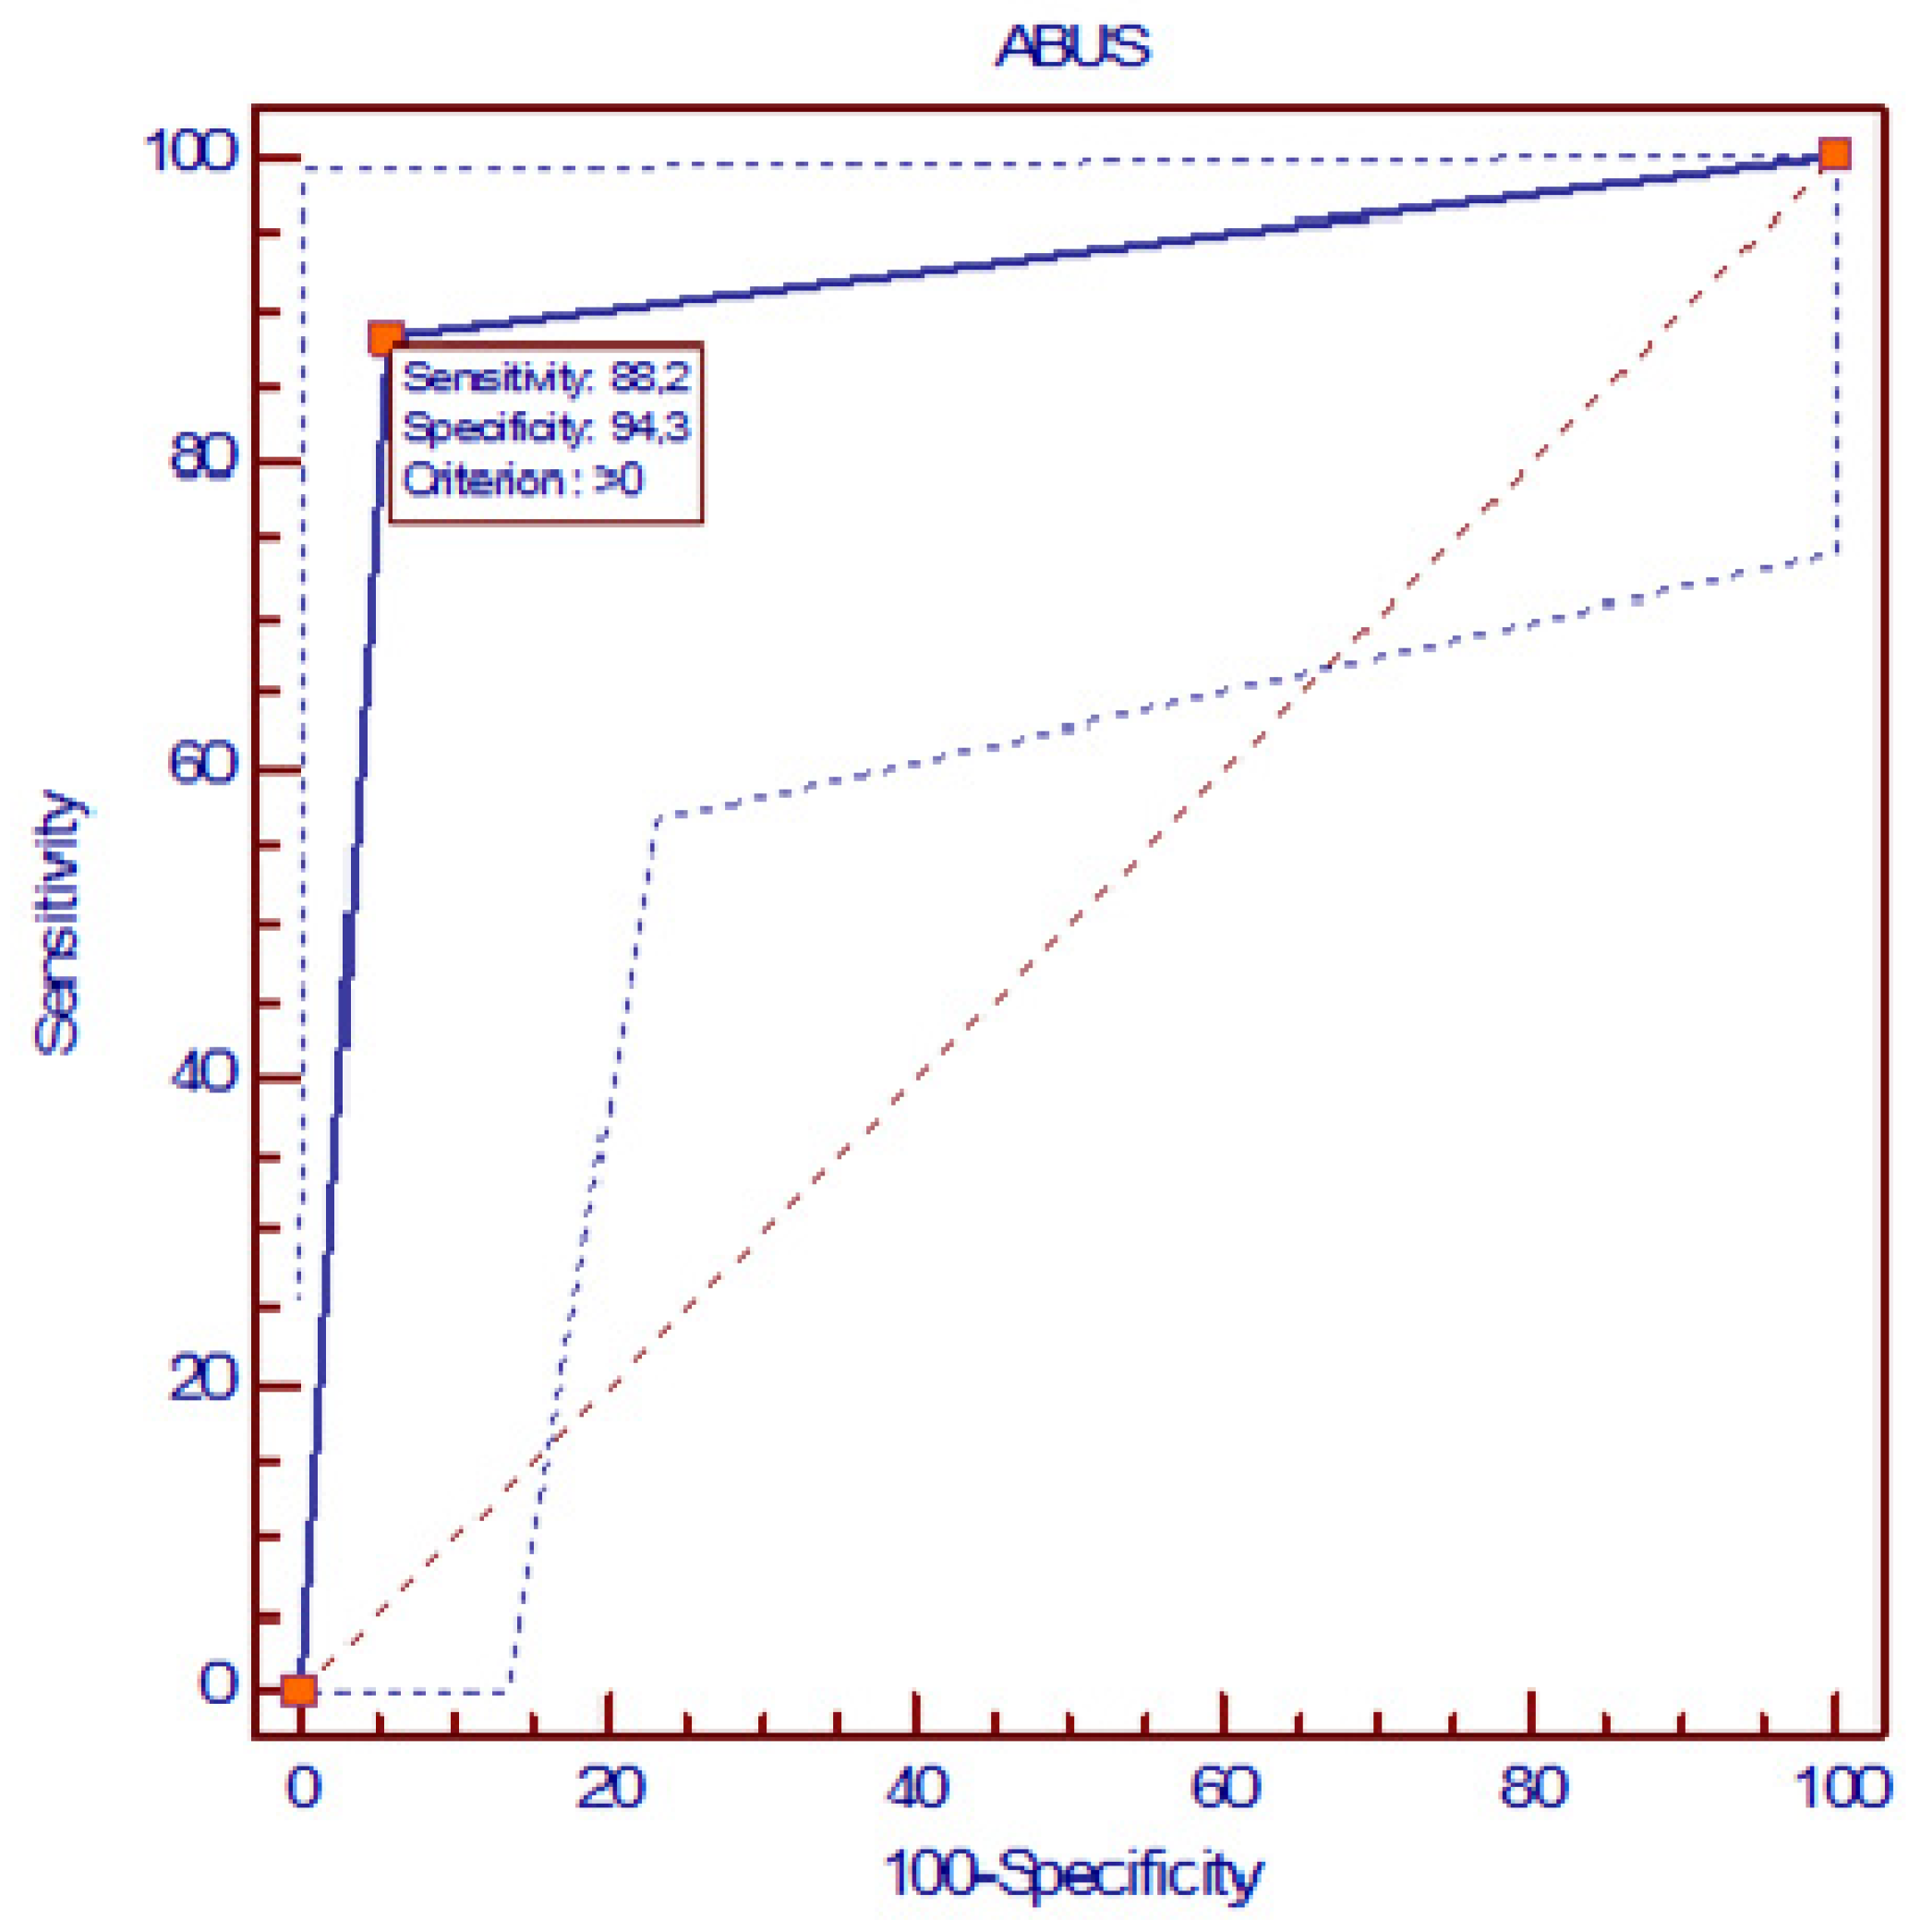

3. Results

4. Discussion

5. Conclusions